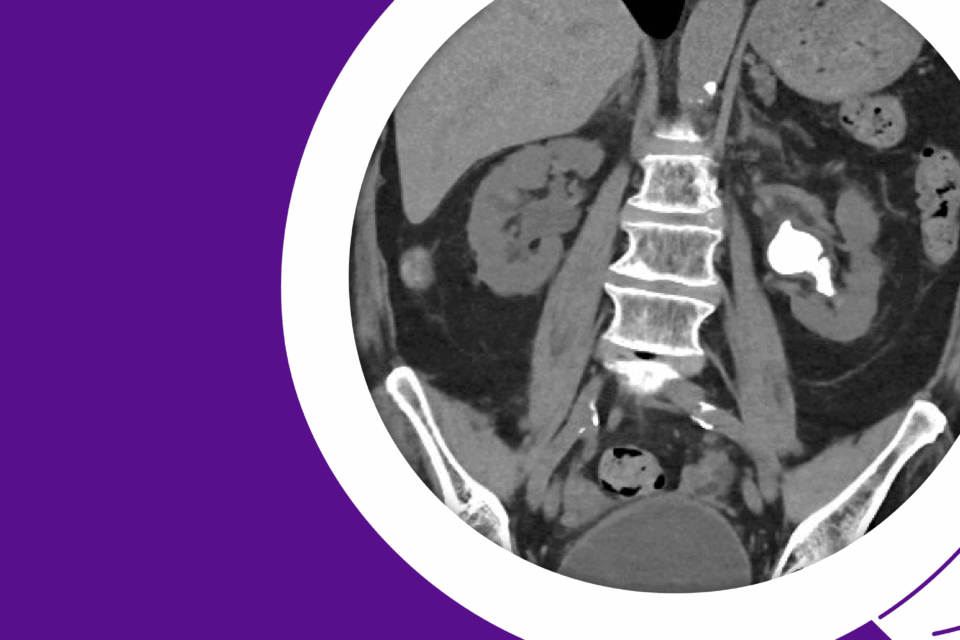

Robotic Management of Giant Hydronephrosis & Contralateral UPJ Obstruction

Dr. Brian W. Chao details his approach to robotic nephrectomy and pyeloplasty for incidentally discovered giant hydronephrosis and contralateral UPJ obstruction.